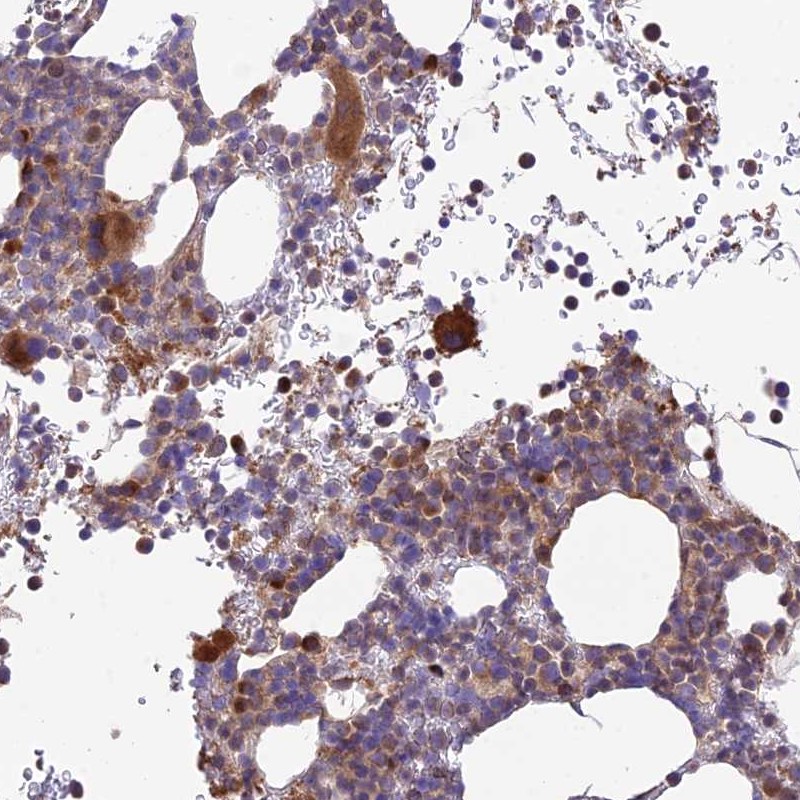

Immunohistochemical staining of human bone marrow shows strong cytoplasmic positivity in hematopoietic cells.